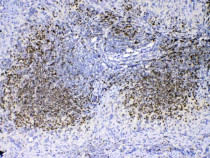

ARG41677 anti-PAX5 antibody IHC-P image

Immunohistochemistry: Paraffin-embedded Human tonsil tissue. Antigen Retrieval: Heat mediation was performed in Citrate buffer (pH 6.0, epitope retrieval solution) for 20 min. The tissue section was blocked with 10% goat serum. The tissue section was then stained with ARG41677 anti-PAX5 antibody at 1 µg/ml dilution, overnight at 4°C.